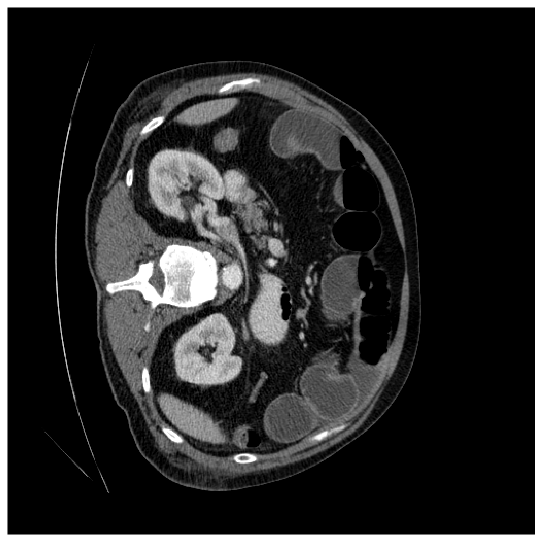

Our model is evaluated on the Synapse [25] and ACDC [24] datasets. Synapse is an abdominal CT image dataset with 30 images containing eight organs: the aorta, gallbladder (GB), left kidney (KL), right kidney (KR), liver, pancreas (PC), spleen (SP), and stomach (SM). 18 and 12 scans are used for training and evaluation, respectively. ACDC provides MRI data containing three organs of 100 patients: the right ventricle (RV), left ventricle (LV), and myocardium (Myo). 70 images for training, 10 for validation, and 20 images for evaluation are used.

where and denote the fuzzy window patch extracted from the original image and the pixel at coordinates in the original image , respectively. is the scaling factor defined as the ratio of the desired uniform variance to the fuzzy variance , and is the translation factor, where represents the fuzzy mean. In the logarithmic model, the operator represents scalar multiplication. The membership function calculator, , is weighted based on how each transformed fuzzy window contributes to the final enhanced image. As a result, the enhanced image exhibits improved quality and a distinct feature distribution compared to the original image. The original and enhanced images are shown in Fig. 14(a) and Fig. 14(b), respectively. As shown in Fig. 14(b), the image quality is enhanced by Eq. (12), emphasizing the organ’s attributes, including shape and intensity. Consequently, previously subtle features in Fig. 14(a), become more pronounced in Fig. 14(b). When these two images are processed through their respective encoders, they generate feature maps characterized by diverse feature distributions and unique information. In other words, the boundary information is better preserved in the original image, while the enhanced image highlights the object’s details. Thus, cross-learning the information from both images leads to improved performance. Please kindly refer to [36] for more details.